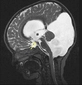

Omurga Disk Sıvısı Nedir ve Ne İşe Yarar?Omurga disk sıvısı, omurgayı oluşturan disklerin iç kısmında bulunan ve önemli bir biyomoleküler madde olarak öne çıkan bir sıvıdır. Bu sıvı, omurga sağlığı ve işlevselliği açısından kritik bir rol oynamaktadır. Omurga disk sıvısı, disklerin mekanik özelliklerini destekler, şok emici bir işlevi vardır ve omurga hareketliliğini artırır. Omurga Disklerinin YapısıOmurga, omurlar adı verilen 33 ayrı kemikten oluşur ve bu omurlar arasında bulunan diskler, vücudumuzun en önemli destek yapılarından biridir. Diskler, iki ana kısımdan oluşur: dış kısım (anulus fibrosus) ve iç kısım (nucleus pulposus). Disk sıvısı, nucleus pulposus içinde bulunur ve bu kısım, viskoelastik özelliklere sahip bir jeldir. Omurga Disk Sıvısının İşlevleriOmurga disk sıvısı, birçok önemli işlevi yerine getirir: